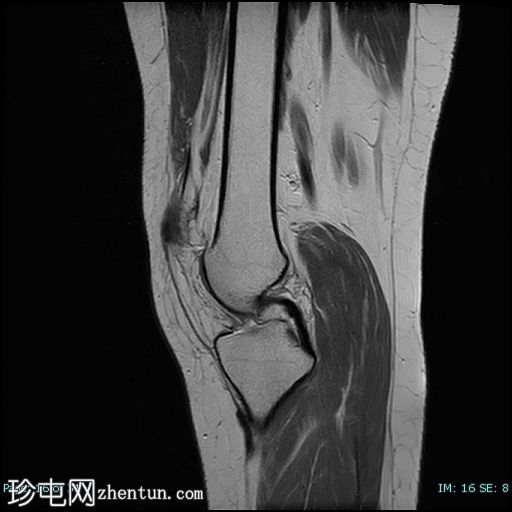

矢状位

STIR序列

髌骨高位(Insall-Salvati比值=1.7),伴外侧半脱位。内侧髌骨支持带及内侧髌股韧带变薄、缺损、松弛。

外侧髌骨关节面软骨内T2/STIR/PD信号强度增高,伴下方骨髓囊性改变和水肿。

外侧Hoffa脂肪垫水肿。

外侧髌骨关节面软骨软化。

股四头肌腱和髌腱正常。

十字韧带和侧副韧带厚度、走行和信号强度正常。

半月板厚度和信号强度正常。

关节周围肌肉和肌腱显影正常。腘窝神经血管束正常。未见贝克囊肿。

本病例展示了霍夫脂肪垫撞击综合征的典型特征,伴有髌骨高位和髌骨外侧半脱位。

患者症状最常见的潜在病因被认为是髌骨轨迹异常。